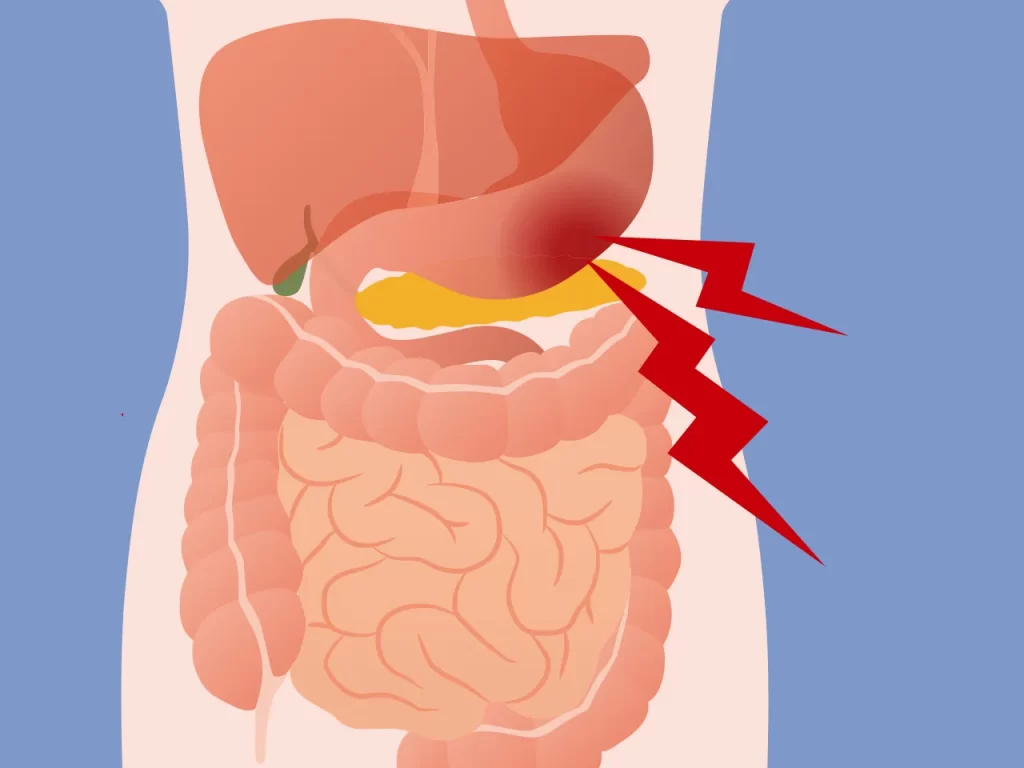

نغطي كل التخصصات الطبية

ان شبكة الاطباء والمشافي، تمكننا من اختيار افضل علاج باقل كلفة ممكنة

استیعاب کافة الحالات الطبیة لشمولیة التخصصات